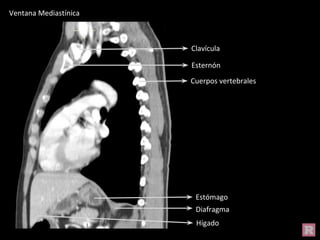

Hígado

Tráquea

Esternón

Pulmón der

Ventana Mediastínica

Estómago

Diafragma

Clavícula

Cuerpos vertebrales